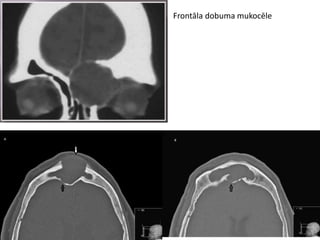

Klīniskā gadījuma apraksts

Paciente, 37 gadus veca

Vēršas vienā no Rīgas privātklīnikām, lai veiktu

estētisko blefaroplastiku ( plākstiņu noslīdēšana,

izteiktāk kreisajā pusē)

Citas sūdzības:

• Periodiska deguna obstrukcija

• Elpošanas grūtības caur degunu

• Izdalījumi no deguna

• Spiedošas sāpes kreisajā sejas pusē (īpaši

izteiktas supraorbitāli, frontāla dobuma

projekcijas vietā)

 CT

 MRI

CT

CT I

CT II

MRI

Paciente, 37 gadusveca Vēršas vienā no Rīgas privātklīnikām, lai veiktu estētisko blefaroplastiku ( plākstiņu noslīdēšana, izteiktāk kreisajā pusē)

Citas sūdzības: • Periodiskadeguna obstrukcija • Elpošanas grūtības caur degunu • Izdalījumi no deguna • Spiedošas sāpes kreisajā sejas pusē (īpaši izteiktas supraorbitāli, frontāla dobuma projekcijas vietā)  CT  MRI